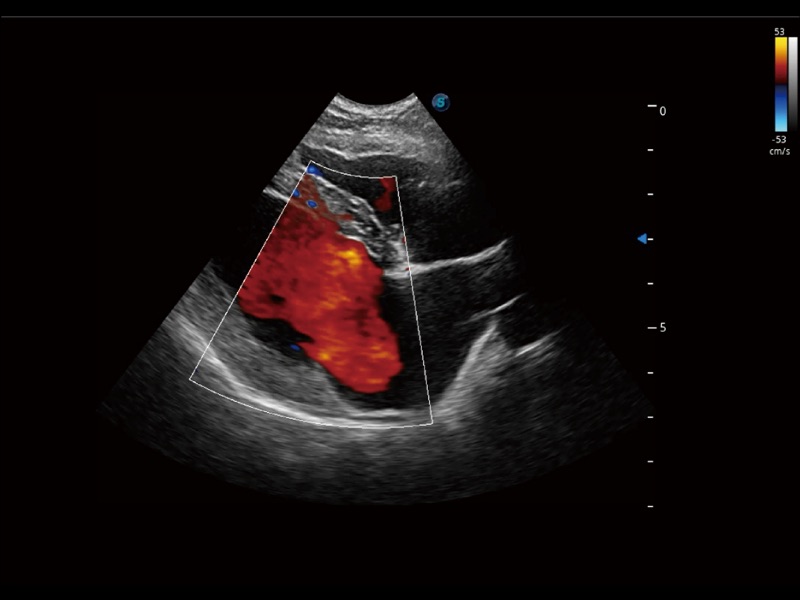

通过创新的 Matrix E自适应滤波器和超长时间域算法,极大提升超低速微细血流的检出能力,同时更精准地滤除软组织和噪声信号,为兽用医生提供以往无法通过常规血流获得的疾病诊断信息。

通过色彩血流和实时宽景相结合,可观察到完整的静脉或动脉的血流,方便医生检查。实时扫查过程中,如有任何操作失误也可以很容易地进行回扫擦除,而不会中断扫查。